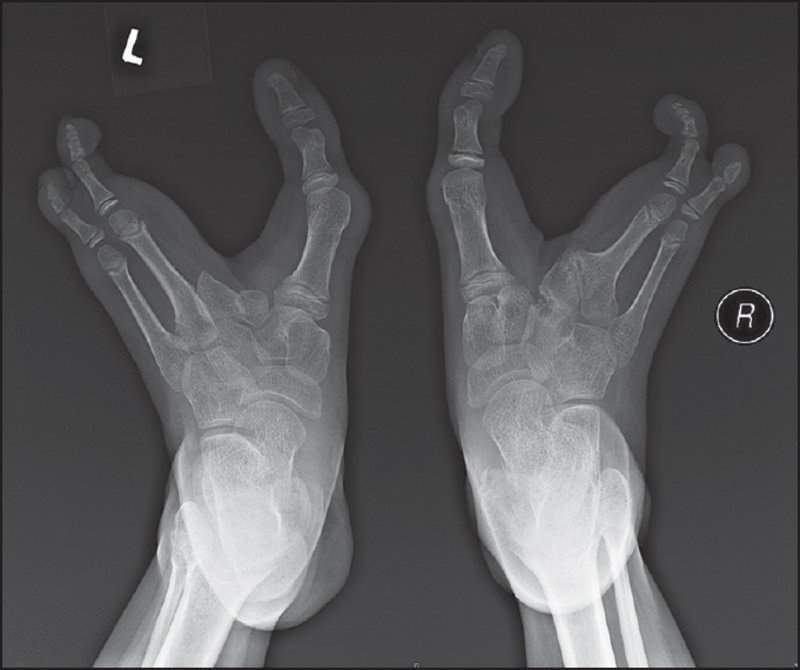

وتتميز هذه القبيلة بحالة وراثية نادرة تُعرف باسم "انعدام الأصابع"؛ حيث تغيب الثلاث أصابع التي في منتصف القدم، أما الإصبعان الخارجان فنجدهما منحنيين إلى الداخل فيما يشبه قدم النعامة؛ مما جعلهم يشتهرون بـ"شعب النعامة".

وكان السبب وراء ظهور تلك الحالة الوراثية الغريبة أن قانون القبيلة؛ أوجَبَ عليهم أن يتزوج الأقارب من القبيلة فقط، وما زالت تلك الحالة باقية حتى الآن نتيجة لاستمرار شعب الفادوما في تنفيذ هذا القانون.

ويعيش هذا الشعب حياته بشكل طبيعي للغاية، ولا تمثل تلك الحالة النادرة مشكلة صحية لديهم، ولا تعوق حركاتهم؛ بل يساعدهم شكل أقدامهم على تسلق الأشجار؛ لكنهم لا يستطيعون الركض، ولا يستخدمون النعال أو الأحذية.